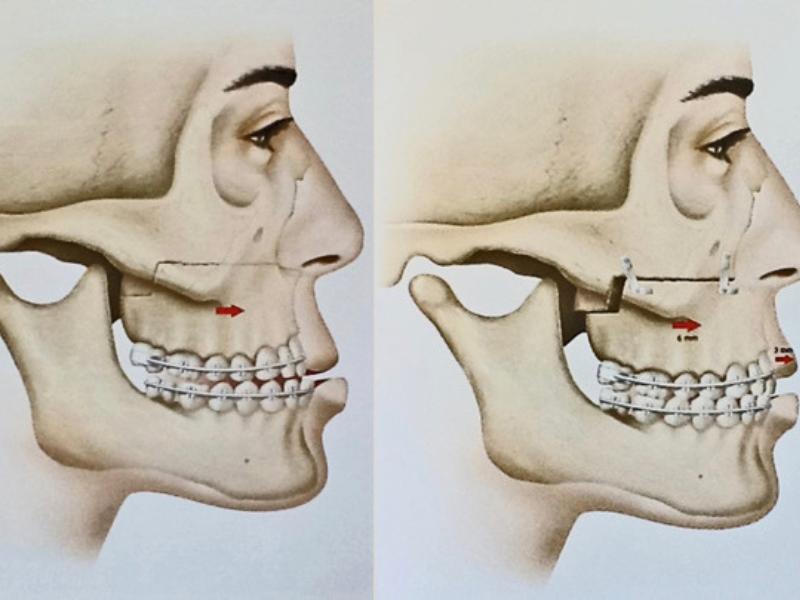

A cirurgia ortognática é um procedimento orto-cirúrgico com o intuito de restabelecer um padrão dentário e facial harmônicos, em pacientes que apresentam alterações no desenvolvimento dessa região. Destacamos uma significativa melhora nos seguintes casos: oclusão (mordida), respiração, DTM´s (disfunções temporomandibulares), harmonia da face. Cirurgia ortognática é um tratamento realizado por meio da combinação de movimentos dentários (ortodontia) e reposicionamento das estruturas dos maxilares (cirurgia). Aproximadamente 20% da população e apresentam vários graus de comprometimento estético e funcional.